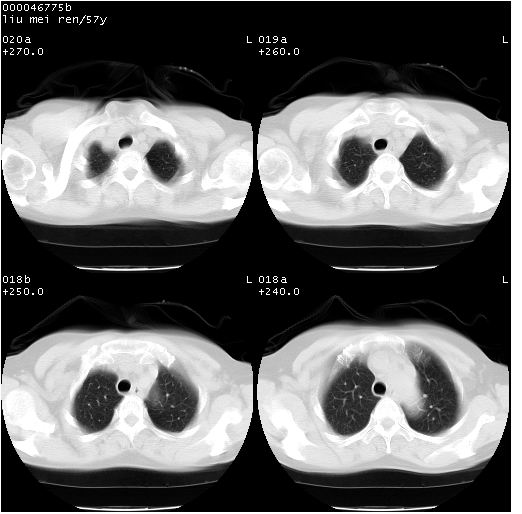

患者 女,57岁。因车祸受伤,其家属要求行“全身ct检查”。平素健康。

胸部ct轴位平扫(层厚10mm,螺距1.5,重建间隔10mm),图像如下:

上腔静脉变异

左位上腔静脉,先天变异。

左位上腔静脉,先天变异。与双侧上腔静脉区别。